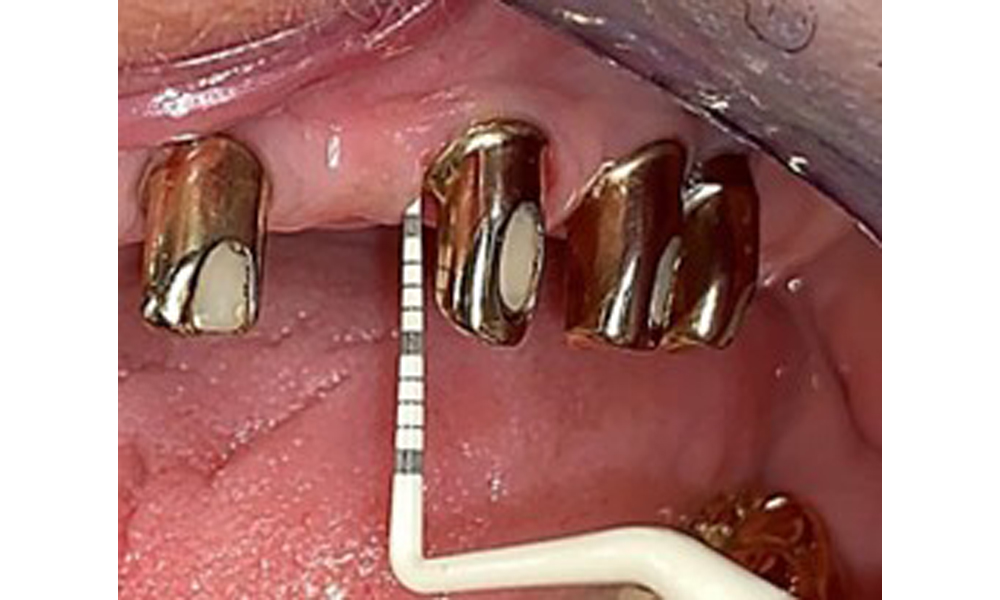

Occlusal view: Maxilla with removable, palateless denture.

Fig. 3: Occlusal view: Maxilla with removable, palateless denture.

The dental findings are as follows: Combined removable implant and tooth-supported telescopic prostheses on implants 15, 13, 21, 23, 24, 25 and tooth 11 (Fig. 1, Fig. 2, Fig. 3). The patient was fitted with a fixed mandibular denture. Adequate bridges were present over 37 to 34 and 45 to 47 (Fig. 4), the crown margins were intact and there were no active caries. A composite filling with a marginal gap was present on tooth 43. There was mandibular gingival recession, exposing 1 to 3 mm of root surface. This also applies to 11.